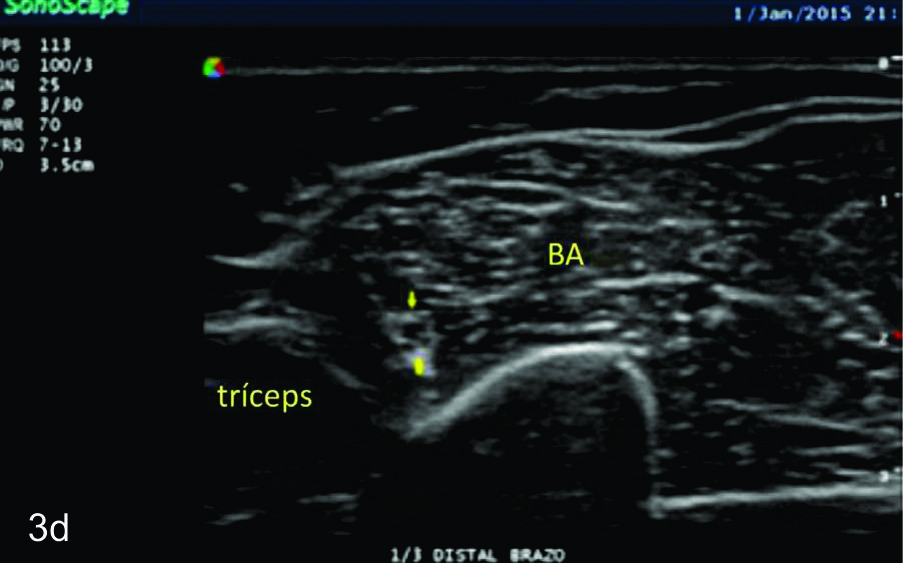

Figura 3

Nervio radial

Serie de cortes axiales del nervio radial desde su origen a nivel del hueco axilar hasta su bifurcación en sus dos ramas terminales a nivel del codo. Se identifica el mismo señalado por flechas amarillas y con las letras NR. AH-arteria humeral, tríceps- músculo tríceps, BA- músculo braquial anterior, CB- músculo coraco braquial, BR- músculo braquiorradial. A- axila, B- tercio proximal del brazo, C- tercio medio del brazo, D- tercio distal del brazo, E- codo, las flechas señalan las dos ramas terminales del nervio radial.